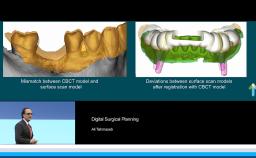

Digital or computer-guided surgery has been widely used in maxillofacial surgery with great enthusiasm. There is substantial benefit to digital planning and surgical guide usage in mandibular reconstructions with fibula grafts. Benefits of guided surgery are presented through multiple case presentations during this lecture. Digital surgical guides include both mandibular resection guides, fibula harvesting guides, and customized milled titanium plates for mandibular fixation. Surgical guides are improving the accuracy of such complex operations, as precise bone-to-bone contact is crucial to the success of these surgical procedures. They substantially influence the efficiency of the surgical procedure and shorten the time needed to perform complex surgical treatments, which often involve two surgical teams.